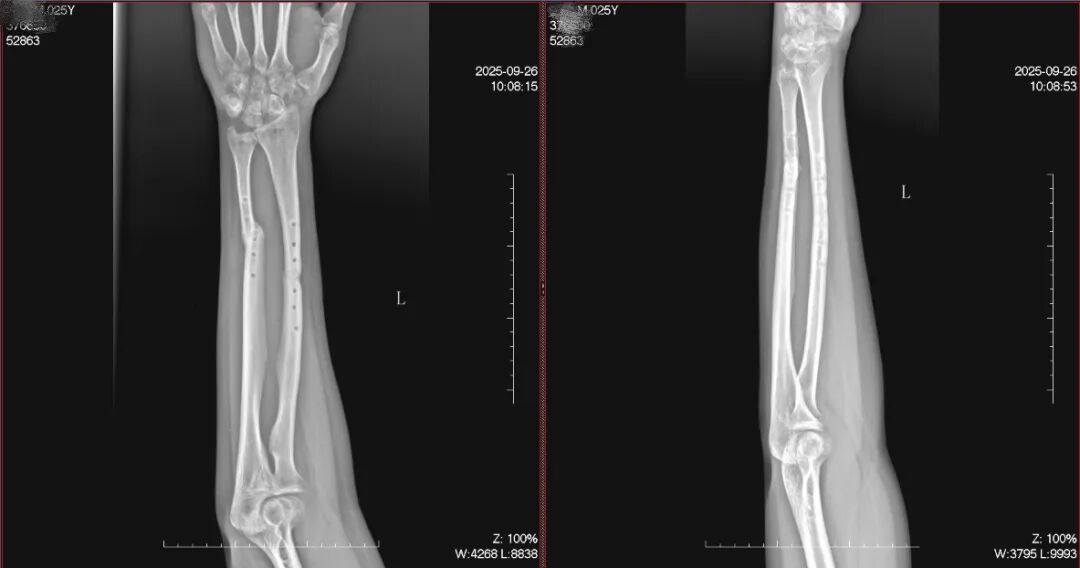

经过近12周的密切诊疗和循序渐进的康复,王先生前臂肿胀疼痛迅速消退,复查X光片显示:左尺桡骨中下段呈内固定取出术后改变,断端对位对线可,骨折线由清晰逐渐模糊,肘关节、腕关节对应关系良好。

又经过2个月,再次复查,骨折断端已骨痂生长。

一例儿童尺桡骨双骨折应用手法正骨治疗的病例。